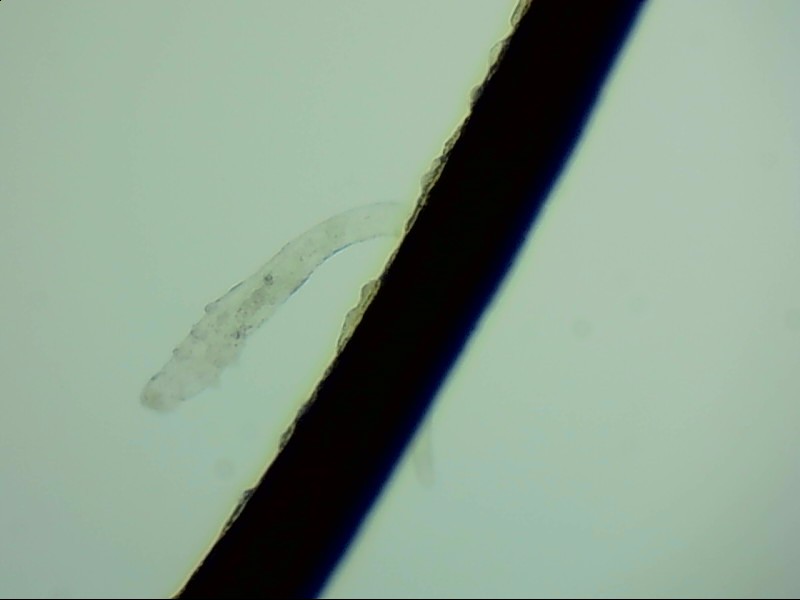

小張是一位程序員,長時間對著電腦,感覺眼干、有異物感在所難免。最近他除了眼干、難受,還發(fā)現(xiàn)眼睛發(fā)癢,掉落的睫毛上還會帶著絲狀的分泌物。剛發(fā)現(xiàn)時小張并沒有放在心上,但當他在屏幕上看到睫毛上的螨蟲時,他的心里一陣后怕,“原來我的睫毛上長著這么可怕的東西。”

螨蟲怎么會爬到睫毛里?廈門眼科中心蠕形螨性瞼緣炎門診張麗穎博士后介紹,人體螨蟲主要有兩種,一種是皮脂螨,主要寄生于皮脂腺和瞼板腺內(nèi);另一種是蠕形螨,“住”在睫毛毛囊里,晚上從毛囊里爬出來,白天躲在毛囊里產(chǎn)卵。

據(jù)介紹,這種疾病確診主要通過觀察睫毛里的螨蟲數(shù)量聯(lián)合瞼緣及眼表情況共同診斷。一般而言,如果12根睫毛里,有2條或是超過2條的螨蟲就可以被確診。如果檢查確實發(fā)現(xiàn)較多的蠕形螨感染,建議加上抗螨治療。張麗穎說,發(fā)現(xiàn)眼睛干澀、發(fā)癢,不要自行用藥,建議到醫(yī)院就診。如果長期反復多發(fā)霰粒腫,要考慮是否存在蠕形螨感染。